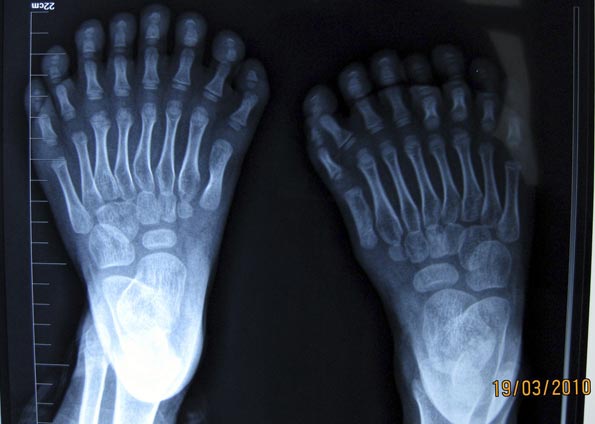

Imagem de raio X tirado no dia 19 mostra os pés de garoto de 6 anos que nasceu com 15 dedos na mão e 16 dedos nos pés na China. (Foto: Reuters)